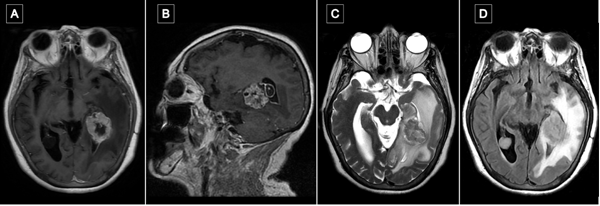

Craneotomía y durotomía

La incisión se centró en el punto temporal posterior (Figura 3), realizándose una herradura frontotemporooccipital izquierda y una cuidadosa hemostasia del colgajo. Craneotomía frontotemporal izquierda. La duramadre fue infiltrada con lidocaína al 1%. Posterior a ello se efectuó una durotomía arciforme con pedículo hacia basal exponiendo el giro temporal superior y medio. Con la paciente despierta se hizo ecografía intraoperatoria para delimitación de los márgenes tumorales, los cuales se identificaron con “tags” (Figura 4).

Figura 3.Punto temporal posterior, posicionamiento. A) Posicionamiento de la cabeza del paciente en cabezal de Mayfield Marcación de incisión centrada en punto temporal posterior (estrella amarilla). B) Se toma como referencia anatómica el conducto auditivo externo (CAE) para medición de punto temporal posterior. C) El punto temporal posterior corresponde topográficamente con el atrio del ventrículo lateral.

Figura 4. Ecografía intraoperatoria y mapeo cortical. A) Utilización de guía ecográfica intraoperatoria para identificar tumor y delimitar sus márgenes (A: Anterior; L: Lateral; M: Medial, P: Posterior). B) Marcación de los límites del tumor con tags de letras (A: Anterior; B: Medial; C: Posterior; D: Inferior) y de las áreas de mapeo positivo con presentación de anomia con dos tags de boca en región posterior de T2. Se expusieron también los giros temporales superior (T1), medio (T2) e inferior (T3) y se optó por corticotomía trans-T2.

Con la paciente despierta, se realizó estimulación cortical utilizando multitarea con flexión y extensión de miembro superior derecho combinando prueba de secuencias automáticas, test de nominación (Boston) y asociación semántica (PPTT). Para ello, se utilizó estimulación bipolar con pulso de onda cuadrada bifásica, de 1 ms de duración y frecuencia de 60 Hz. Se identificó el umbral de estimulación en 3.0 mA tras inducirse anomia en la región posterior de la circunvolución temporal media (T2).(13) Se identificaron áreas de mapeo positivo con los respectivos tags, delimitándose el acceso seguro a través de la porción media del giro temporal medio (ver Figura 4 B).